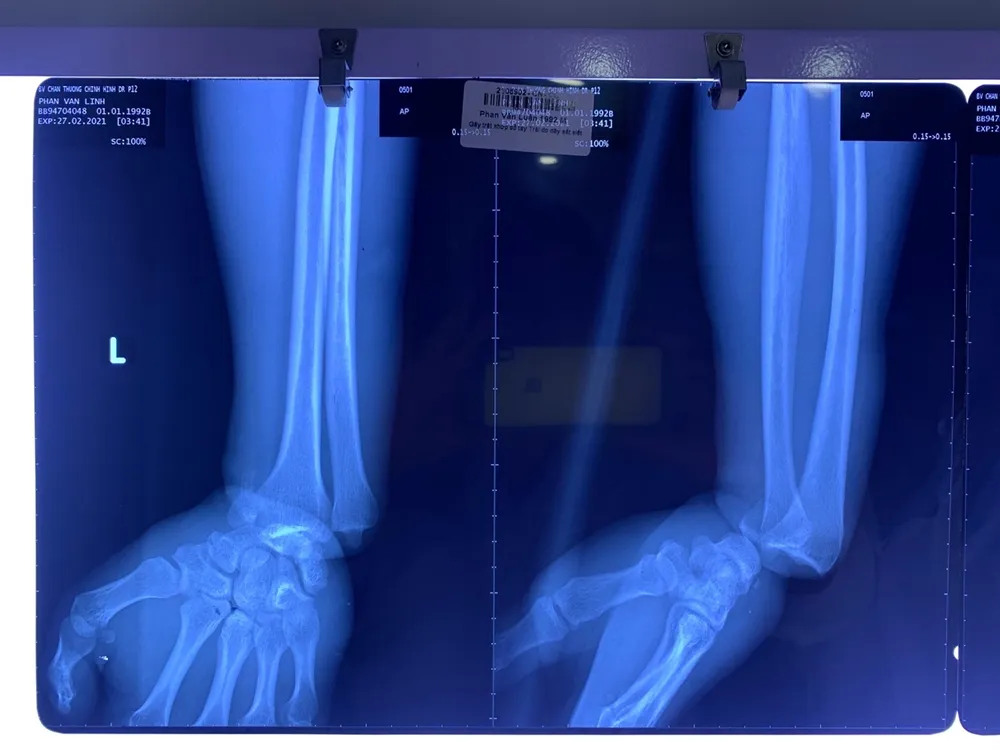

Tai nạn lao động khiến nam thanh niên suýt mất chức nặng vận động tay ảnh 1 Hình chụp X-quang bệnh nhân bị gãy trật khớp cổ tay trái

Vùng bàn tay, ngón tay bị tím, thiếu máu nuôi toàn bộ. Bàn tay, ngón tay lạnh, mất chức nặng vận động và cảm giác. Kết quả chẩn đoán hình ảnh cho thấy anh L. bị gãy trật khớp cổ tay trái.